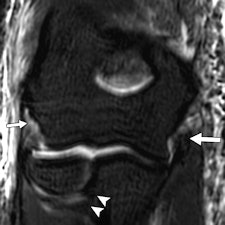

"Elbow injuries in Olympic sports have not been reported previously," noted lead author Dr. Sarath Bethapudi, from the department of musculoskeletal radiology at Leeds Teaching Hospitals National Health Service (NHS) Trust in the U.K. "Most of the injuries resulted from valgus strain with hyperextension of the elbow and usually presented as injuries to the medial joint supporting structures. Combinations of medial and lateral ligaments were seen in combat and power sports with high-energy acute trauma. Such injuries also resulted in tears to secondary stabilizers of the medial joint, including the common flexor tendons and medial muscular compartments" (AJR, September 2013, Vol. 201:3, pp. 535-539).

Significant ligament and tendon injuries to the elbow can occur often in nonthrowing athletes, and most of the elbow injuries seen in these athletes were isolated high-grade ulnar collateral ligament (UCL) injuries, although combinations of medial and lateral ligament injuries can occur, the authors concluded. Ulnar attachment tears were the next most common injuries, followed by midsubstance tears of the UCL. This trend differs from the existing literature, which suggests that midsubstance tears are the most common type of UCL injuries, they wrote.